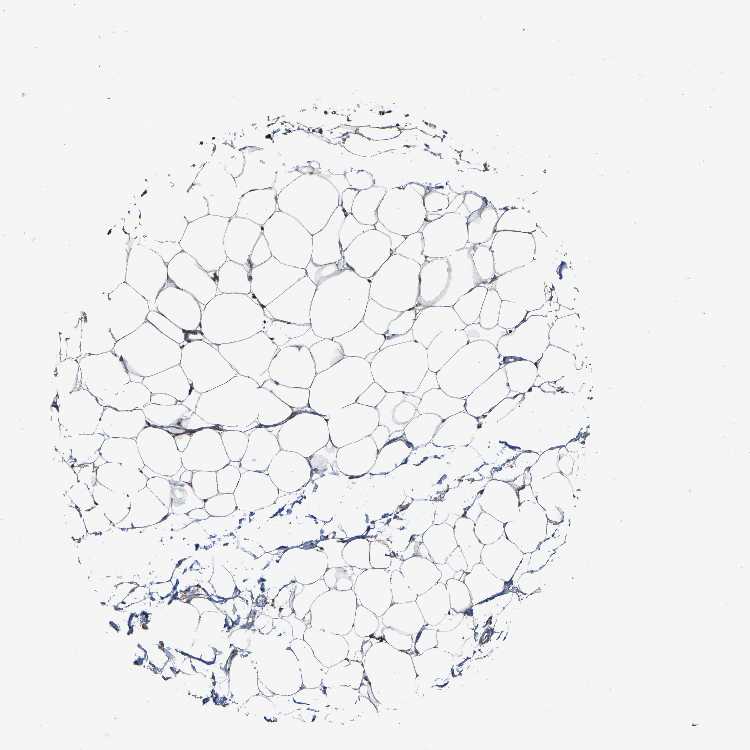

TISSUE PRIMARY DATA SOFT TISSUE Show tissue menu

SOFT TISSUE - Expression summary

SOFT TISSUE 1 - Antibody stainingi

Antibody staining in the annotated cell types in the current human tissue is reported as not detected, low, medium, or high, based on conventional immunohistochemistry profiling in selected tissues. This score is based on the combination of the staining intensity and fraction of stained cells.

Each image is clickable and will lead to virtual microscopy that enables deeper exploration of all samples and also displays staining intensity scores, fraction scores and subcellular localization as well as patient and tissue information for each sample.

Antibody HPA020963Antibody HPA021018

Fibroblasts Not detectedNot detected

Peripheral nerve LowNot detected

SOFT TISSUE 2 - Antibody stainingi

Chondrocytes Not detected-

Fibroblasts HighNot detected